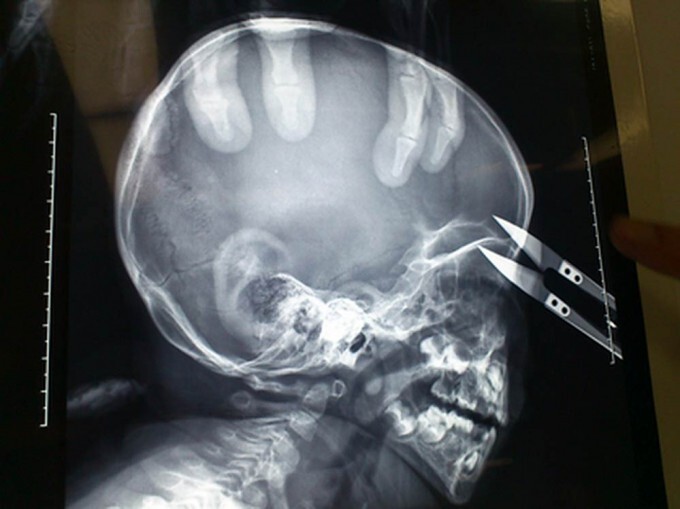

2-летний мальчик чудом выжил после того, как ножницы пронзили его голову в районе глаза. Ван Жиеронг из западной китайской провинции Ганьсу бегал по дому с ножницами, которые он нашел на столе. Неожиданно он споткнулся и упал прямо на ножницы, которые вонзились ему прямо над левым глазом

Мальчика сразу доставили в больницу университета Ланьчжоу в округе Вушань, где врачи провели срочную операцию по удалению ножниц.